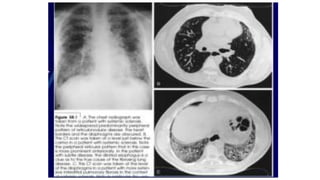

PULMONARY INVOLVEMENT:

25% of lcSSc, 50% dcSSc.

Exertional dyspnea, dry non productive cough.

On examination; bilateral basilar rales.

Three forms:

1. Pulmonary interstitial fibrosis (IPF); dcSS, anti-TOPI

2. Pulmonary hypertension; lcSSc, ACA.

3. Pulmonary alveolitis precede IPF.

Can detected by:

1. HRCT; increase reticular and nodular pattern (ground glass opacity).

2. BAL: increase alveolar macrophage, neutrophil, eosinophil, CD8 T

lymphocyte.

3. Spirometry: ↓FVC, TLC, ↓TLCO >> IPF.

↓TLC>>PH

Pulmonary symptoms can parallel progression of

skin disease